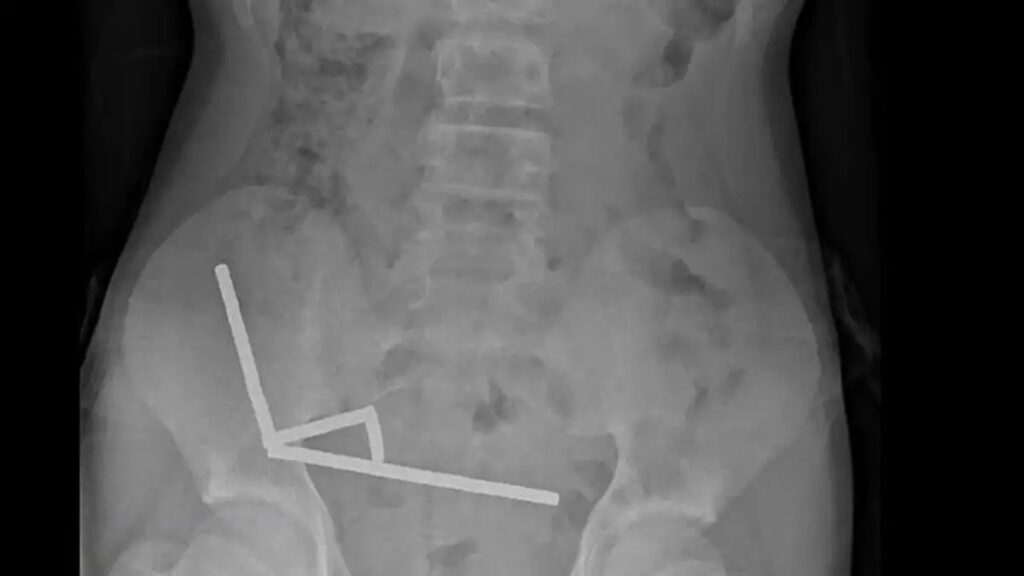

Η ακτινογραφία αποκάλυψε πως οι μαγνήτες είχαν ευθυγραμμιστεί σε τέσσερα ξεχωριστά σημεία στο εσωτερικό του εντέρου, σχηματίζοντας παράλληλες γραμμές.

Σύμφωνα με την ιατρική αναφορά, «φαινόταν ότι βρίσκονταν σε διαφορετικά σημεία του εντέρου, τα οποία είχαν κολλήσει μεταξύ τους λόγω των μαγνητικών δυνάμεων».

Η πίεση που προκάλεσαν οι μαγνήτες οδήγησε σε σοβαρές βλάβες: νέκρωση ιστών σε τέσσερα σημεία του λεπτού εντέρου αλλά και στο τυφλό, το οποίο αποτελεί τμήμα του παχέος εντέρου.